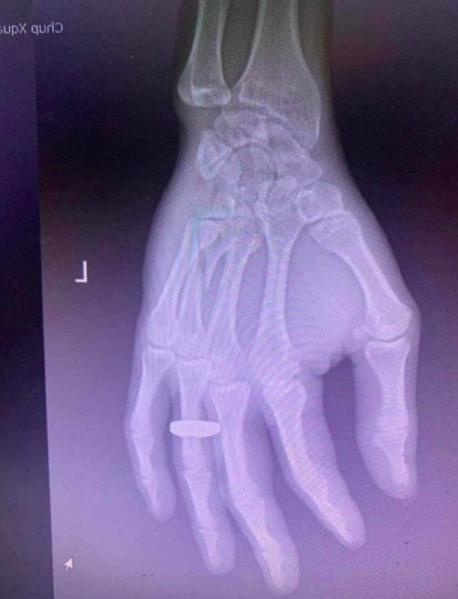

Old  Default Chê vé đắt và đòi xuống xe, hành khách bị nhân viên nhà xe đánh gãy tay

Một nhân viên nhà xe tuyến xe khách Hà Nội - Quảng Ninh đã thẳng tay đánh hành khách chỉ vì anh này cho rằng vé đắt hơn bình thường và đòi xuống xe.

Cụ thể theo nội dung đoạn clip, một nam hành khách lên xe từ Hà Nội đi Móng Cái , Quảng Ninh và phàn nàn rằng vé xe bị đắt. Ngay lập tức một nhân viên nhà xe đã tức giận và đánh đấm liên tục nam hành khách trên. Sự việc chỉ dừng lại khi rất nhiều người trên xe khách lên tiếng. Sau đó, nam hành khách tiếp tục bị nhân viên nhà xe đuổi xuống xe khi chiếc xe khách mới đi đến Bắc Ninh.